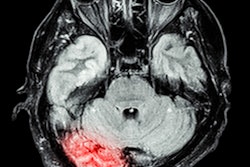

The CARE PMR (Capturing ARIA Risk Equitably with Portable MR) observational study is designed to assess the clinical utility and workflow benefits of Swoop system. Imaging will be performed at infusion centers and clinics to help physicians detect amyloid-related imaging abnormalities (ARIAs) in Alzheimer’s patients.